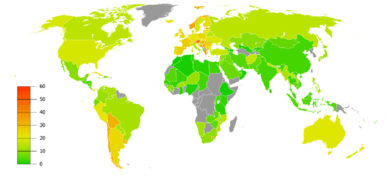

Air pollution

Poorly ventilated cooking fires, often fueled by coal or biomass fuels such as wood and animal dung, lead to indoor air pollution and are one of the most common causes of COPD in developing countries.[36] These fires are a method of cooking and heating for nearly 3 billion people with their health effects being greater among women due to more exposure.[1][36] They are used as the main source of energy in 80% of homes in India, China and sub-Saharan Africa.[8]

People who live in large cities have a higher rate of COPD compared to people who live in rural areas.[37] While urban air pollution is a contributing factor in exacerbations, its overall role as a cause of COPD is unclear.[1] Areas with poor outdoor air quality, including that from exhaust gas, generally have higher rates of COPD.[8] The overall effect in relation to smoking, however, is believed to be small.[1]